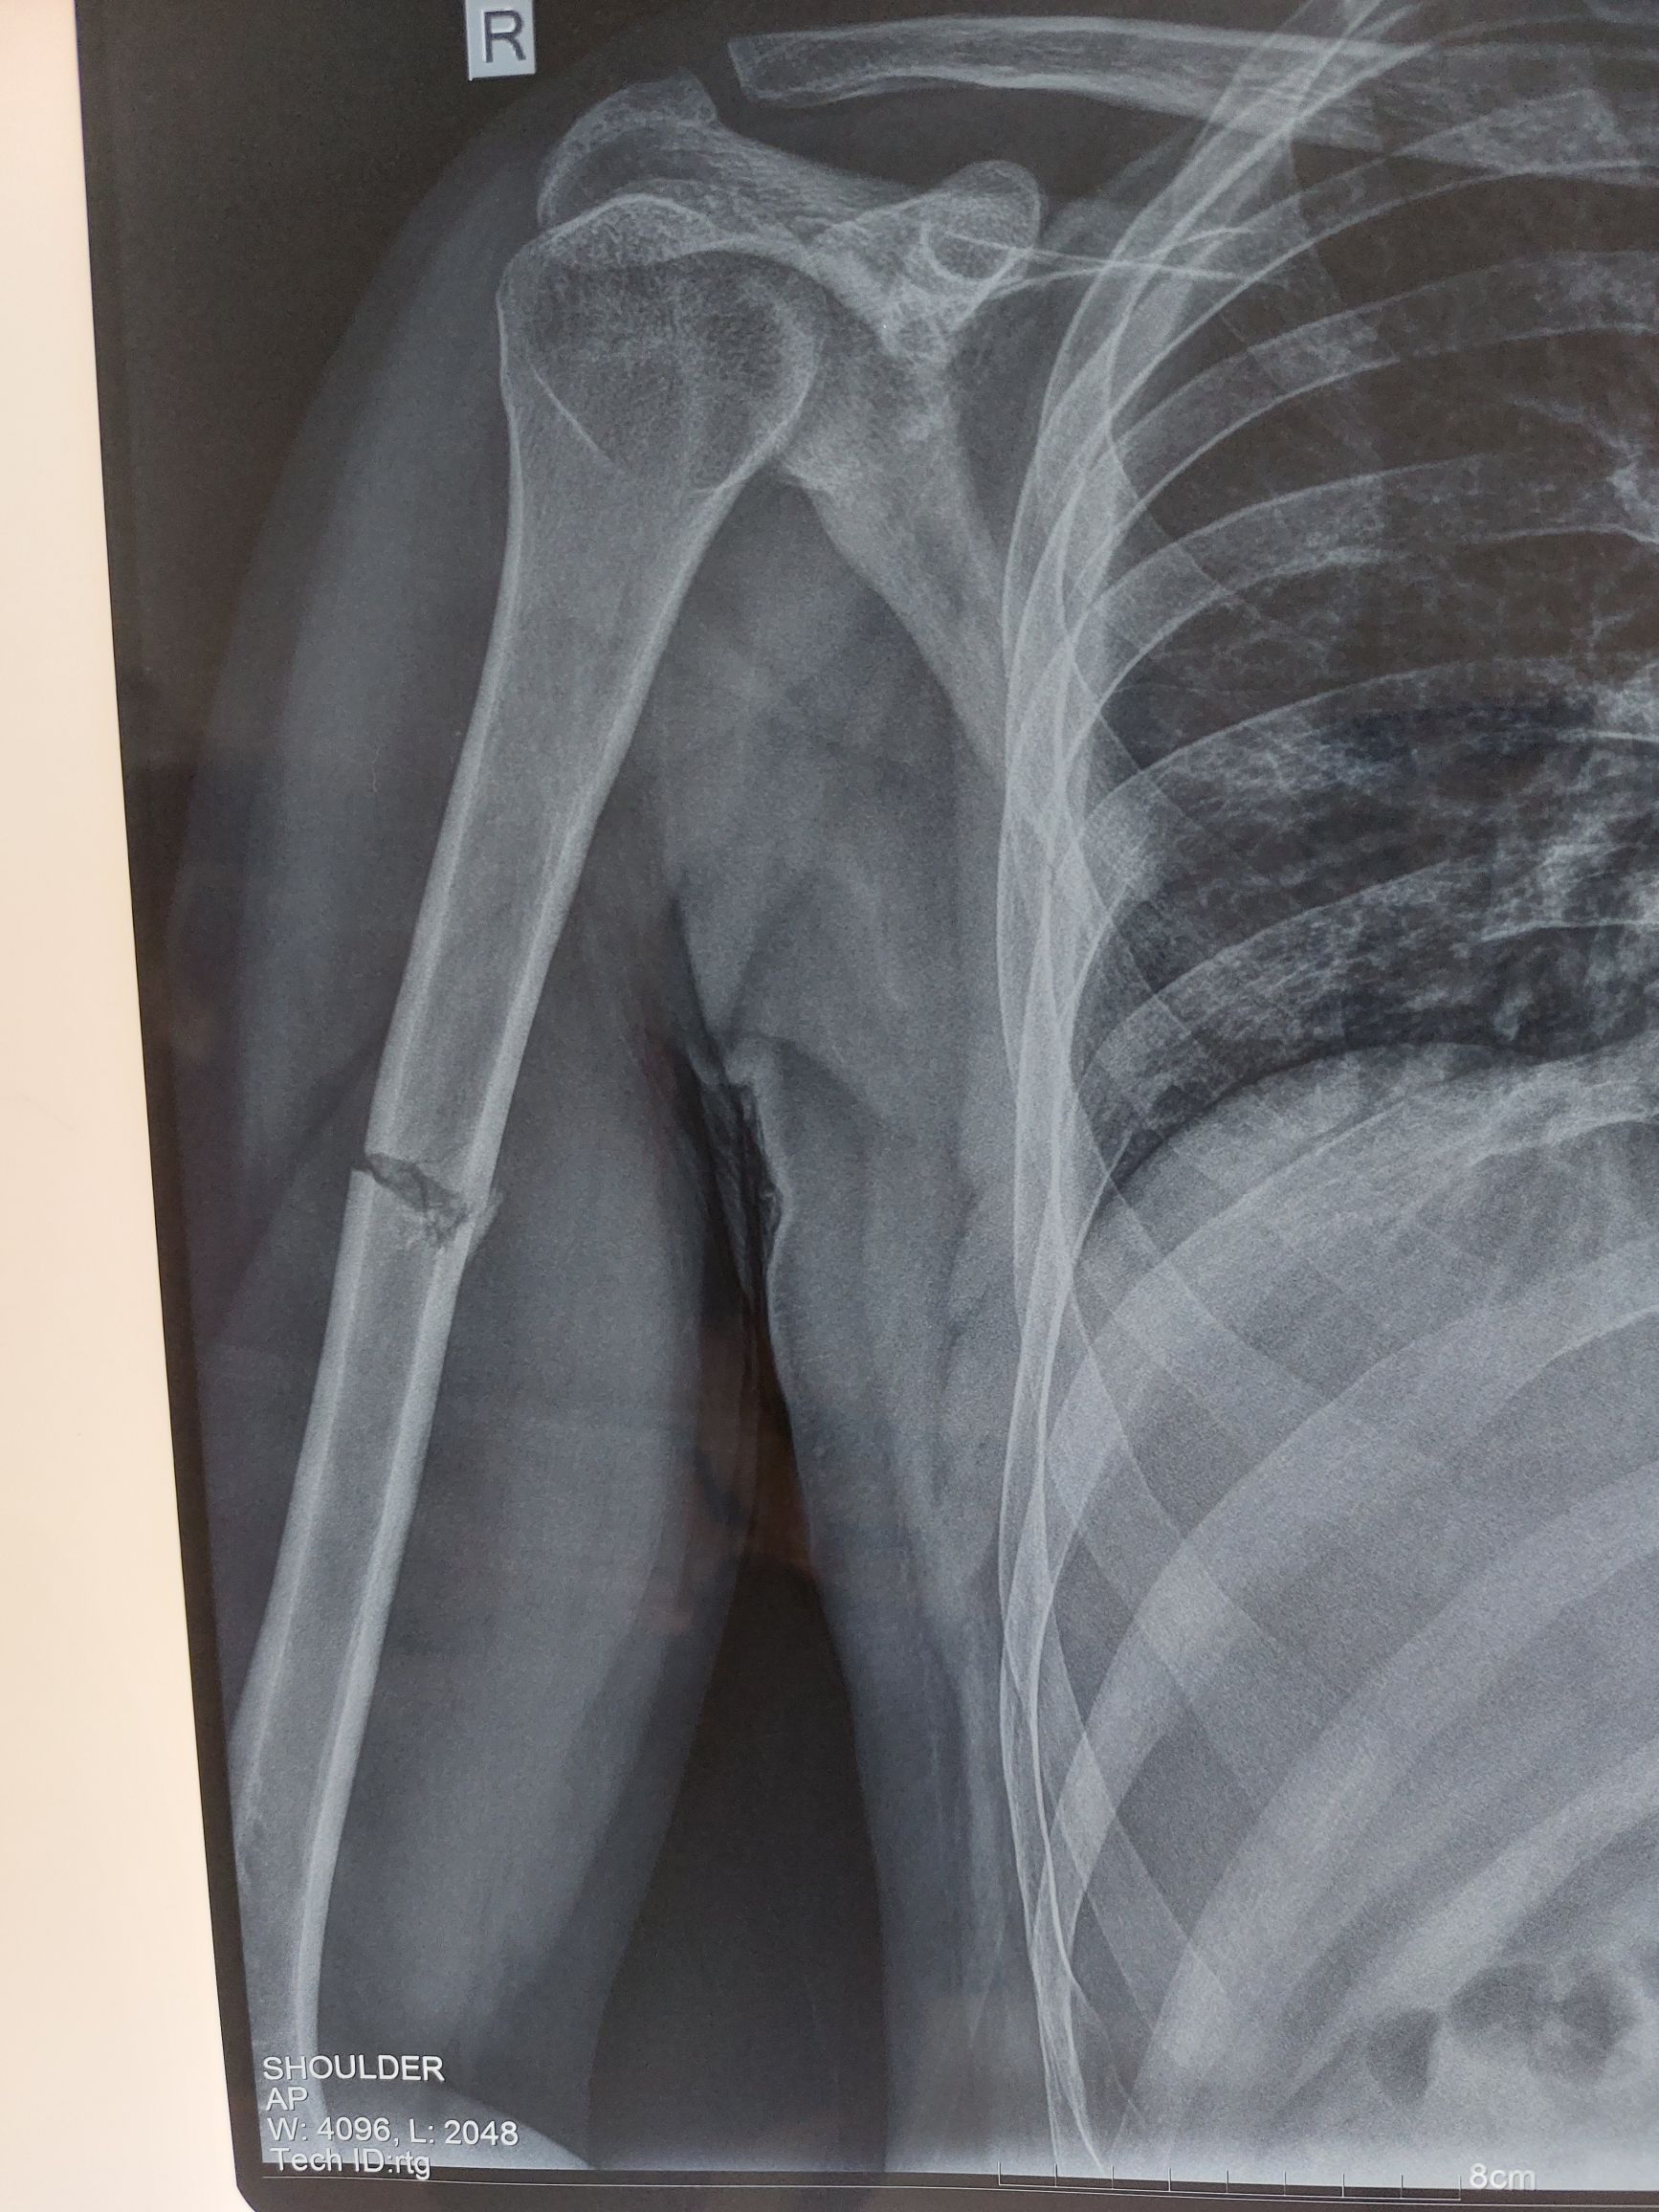

Humerus

Broken Bone

Ortopaedics

Fx Humerus

Fracture of the Humerus Shaft

Humerus Fracture

Mid shaft humerus Fracture